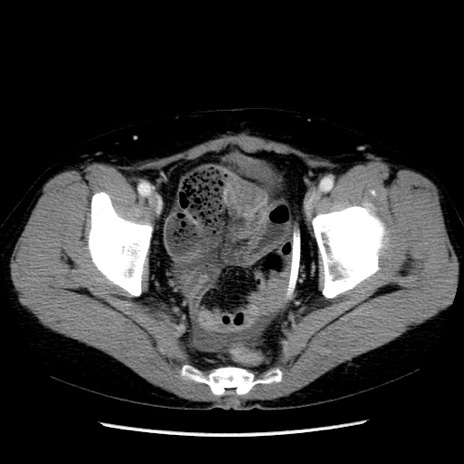

矢状断像